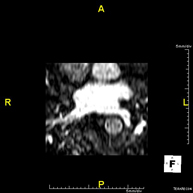

Pulmonary vein MRI angiography

A non-invasive diagnostic test that involves studying the drainage pattern of the pulmonary veins using an electromagnetic field and radio waves (with a transmitter and receiver) and paramagnetic contrast (gadolinium). It is a radiation-free procedure. It is indicated as a preliminary angiographic map in patients who are going to undergo pulmonary vein ablation, as well as in follow-up to rule out the appearance of stenosis.